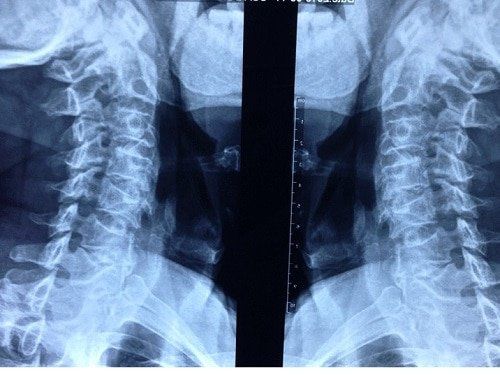

X-ray imaging is a method that employs external radiation to visualize internal changes in bones, joints, and other structures. The X-ray machine emits high-energy X-ray beams, which penetrate soft tissues and bodily fluids to produce images. Dense structures like bone absorb more radiation, reducing the penetration of X-rays.

So, can X-rays detect a herniated disc? This condition arises from the protrusion of the nucleus pulposus beyond the fibrous layer, compressing surrounding structures and causing pain. Consequently, X-rays cannot detect the condition in its early stages, as the spinal structure is minimally affected.

What is the purpose of X-ray imaging in the context of herniated discs? The utility of X-rays is limited to:

•    Diagnosis in cases where the nucleus pulposus has significantly extruded, compressing nerve roots, producing spinal deformities, or narrowing the intervertebral spaces.

•    Furthermore, X-ray images can provide insights into the current alignment of the patient's spine, allowing for preliminary assessments of early signs related to lumbar and cervical disc degeneration.

•    When a contrast agent is injected, radiographs of herniated disc can indirectly visualize the extrusion of the nucleus pulposus and identify any nerve root or spinal cord compression.

•    This diagnostic approach may be optimal for patients with limited financial resources or those residing far from advanced medical facilities, as the obtained images can facilitate provisional diagnoses.